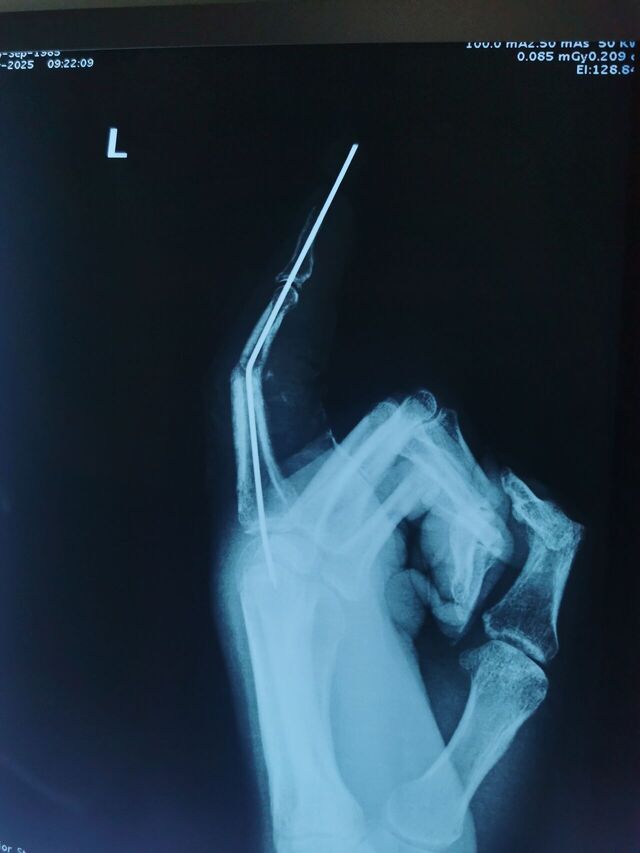

门诊的病人外院(沈阳某医院)手术的

应该是做的关节融合术

不知道如何取出克氏针

给我整不会了